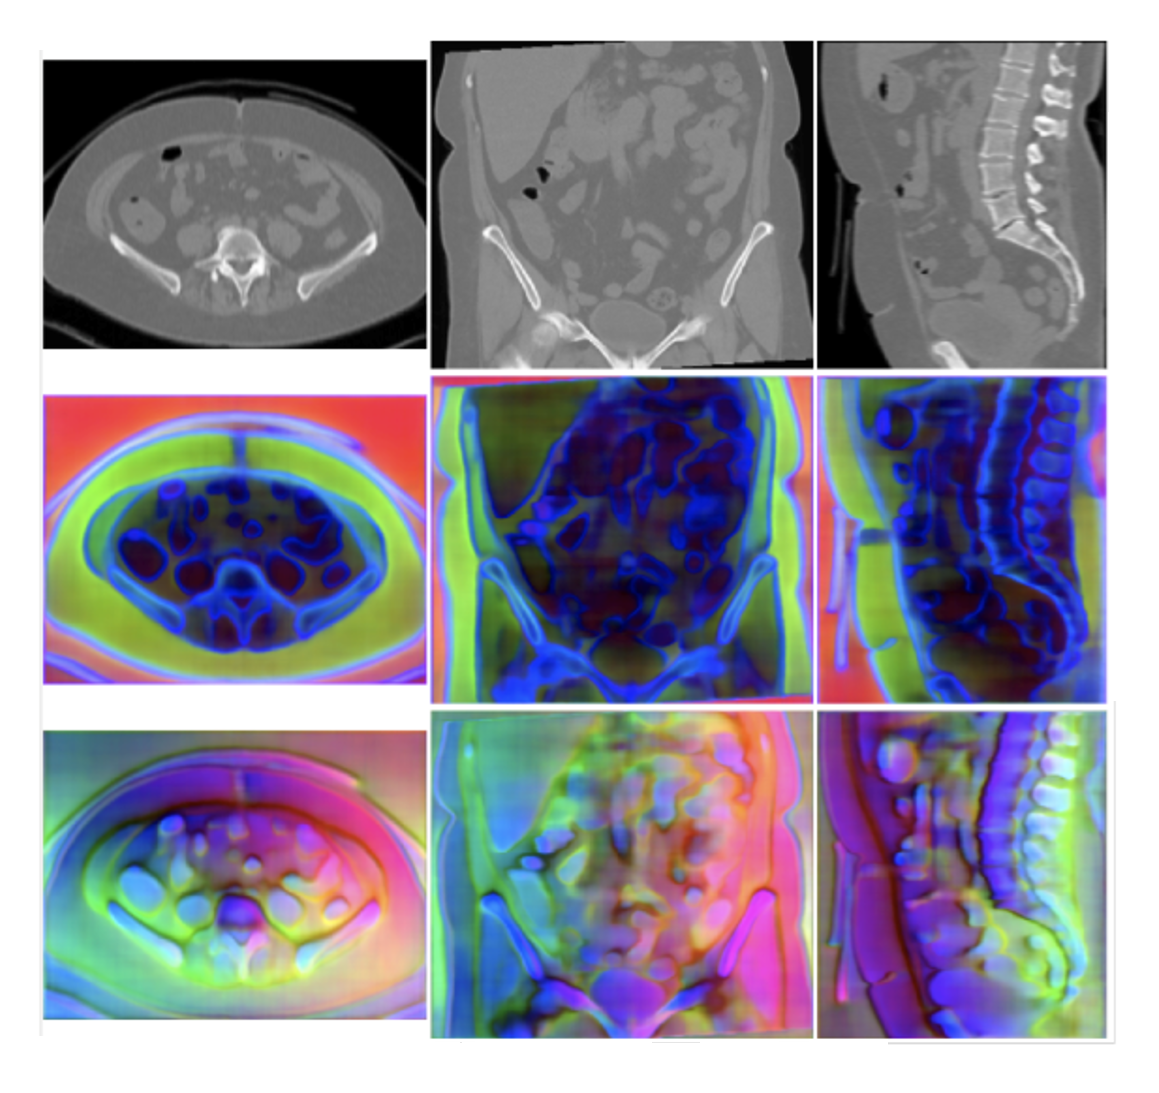

CACTUSS: Common Anatomical CT-US Space for US Examinations

Y. Velikova, W. Simson, M. F. Azampour, P. Paprottka, N. Navab

International Journal of Computer Assisted Radiology and Surgery, 1-9. 2024

Y. Velikova, W. Simson, M. Salehi, M. F. Azampour, P. Paprottka, N. Navab

Medical Image Computing and Computer Assisted Intervention – MICCAI 2022